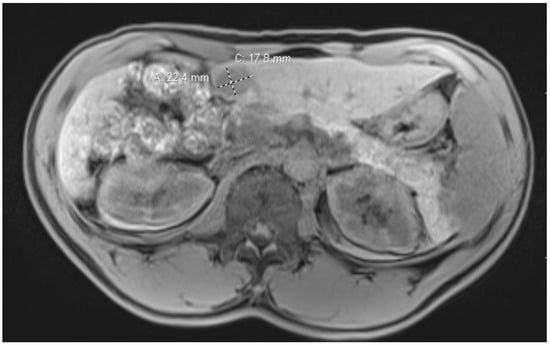

MRI is the most sensitive and specific imaging tool for detecting HCC. Unlike ultrasound and CT, MRI measures the signal intensity of protons at different resonance frequencies, such as fibrosis, steatosis, and water, as seen in Figure 1. This can be useful to differentiate benign liver lesions from metastases. However, patient factors such as claustrophobia, implanted devices, discomfort, and cost may hinder MRI use for diagnostic imaging in liver disease. The Liver Imaging Reporting and Data system (LI-RADS) was developed by the American College of Radiology and later incorporated into the 2018 AASLD HCC clinical practice guidelines as an algorithm for the stratification of the probability of HCC and overall malignancy based on both CT and MRI imaging (Table 1). The LI-RADS algorithms provide a score for liver lesions defined by eight unique diagnostic categories based on imaging ranging from LR-1 (definitely benign) to LR-5 (definitely malignant) []. In terms of diagnostic accuracy, LI-RADS has a sensitivity of 92% and a specificity of 55.5%, as compared to qualitative imaging, which has a sensitivity of 92.3% and a specificity of 41.4%. When used in conjunction, LI-RADS with qualitative imaging has a sensitivity of 97% and a specificity of 30% []. The LI-RADS classification system should be used only for livers with risk factors for HCC such as cirrhosis or chronic HBV infection and not for patients less than 18 years old or with congenital hepatic fibrosis or cirrhosis due to vascular disorders [].

Figure 1.

MRI of a patient with chronic HBV.